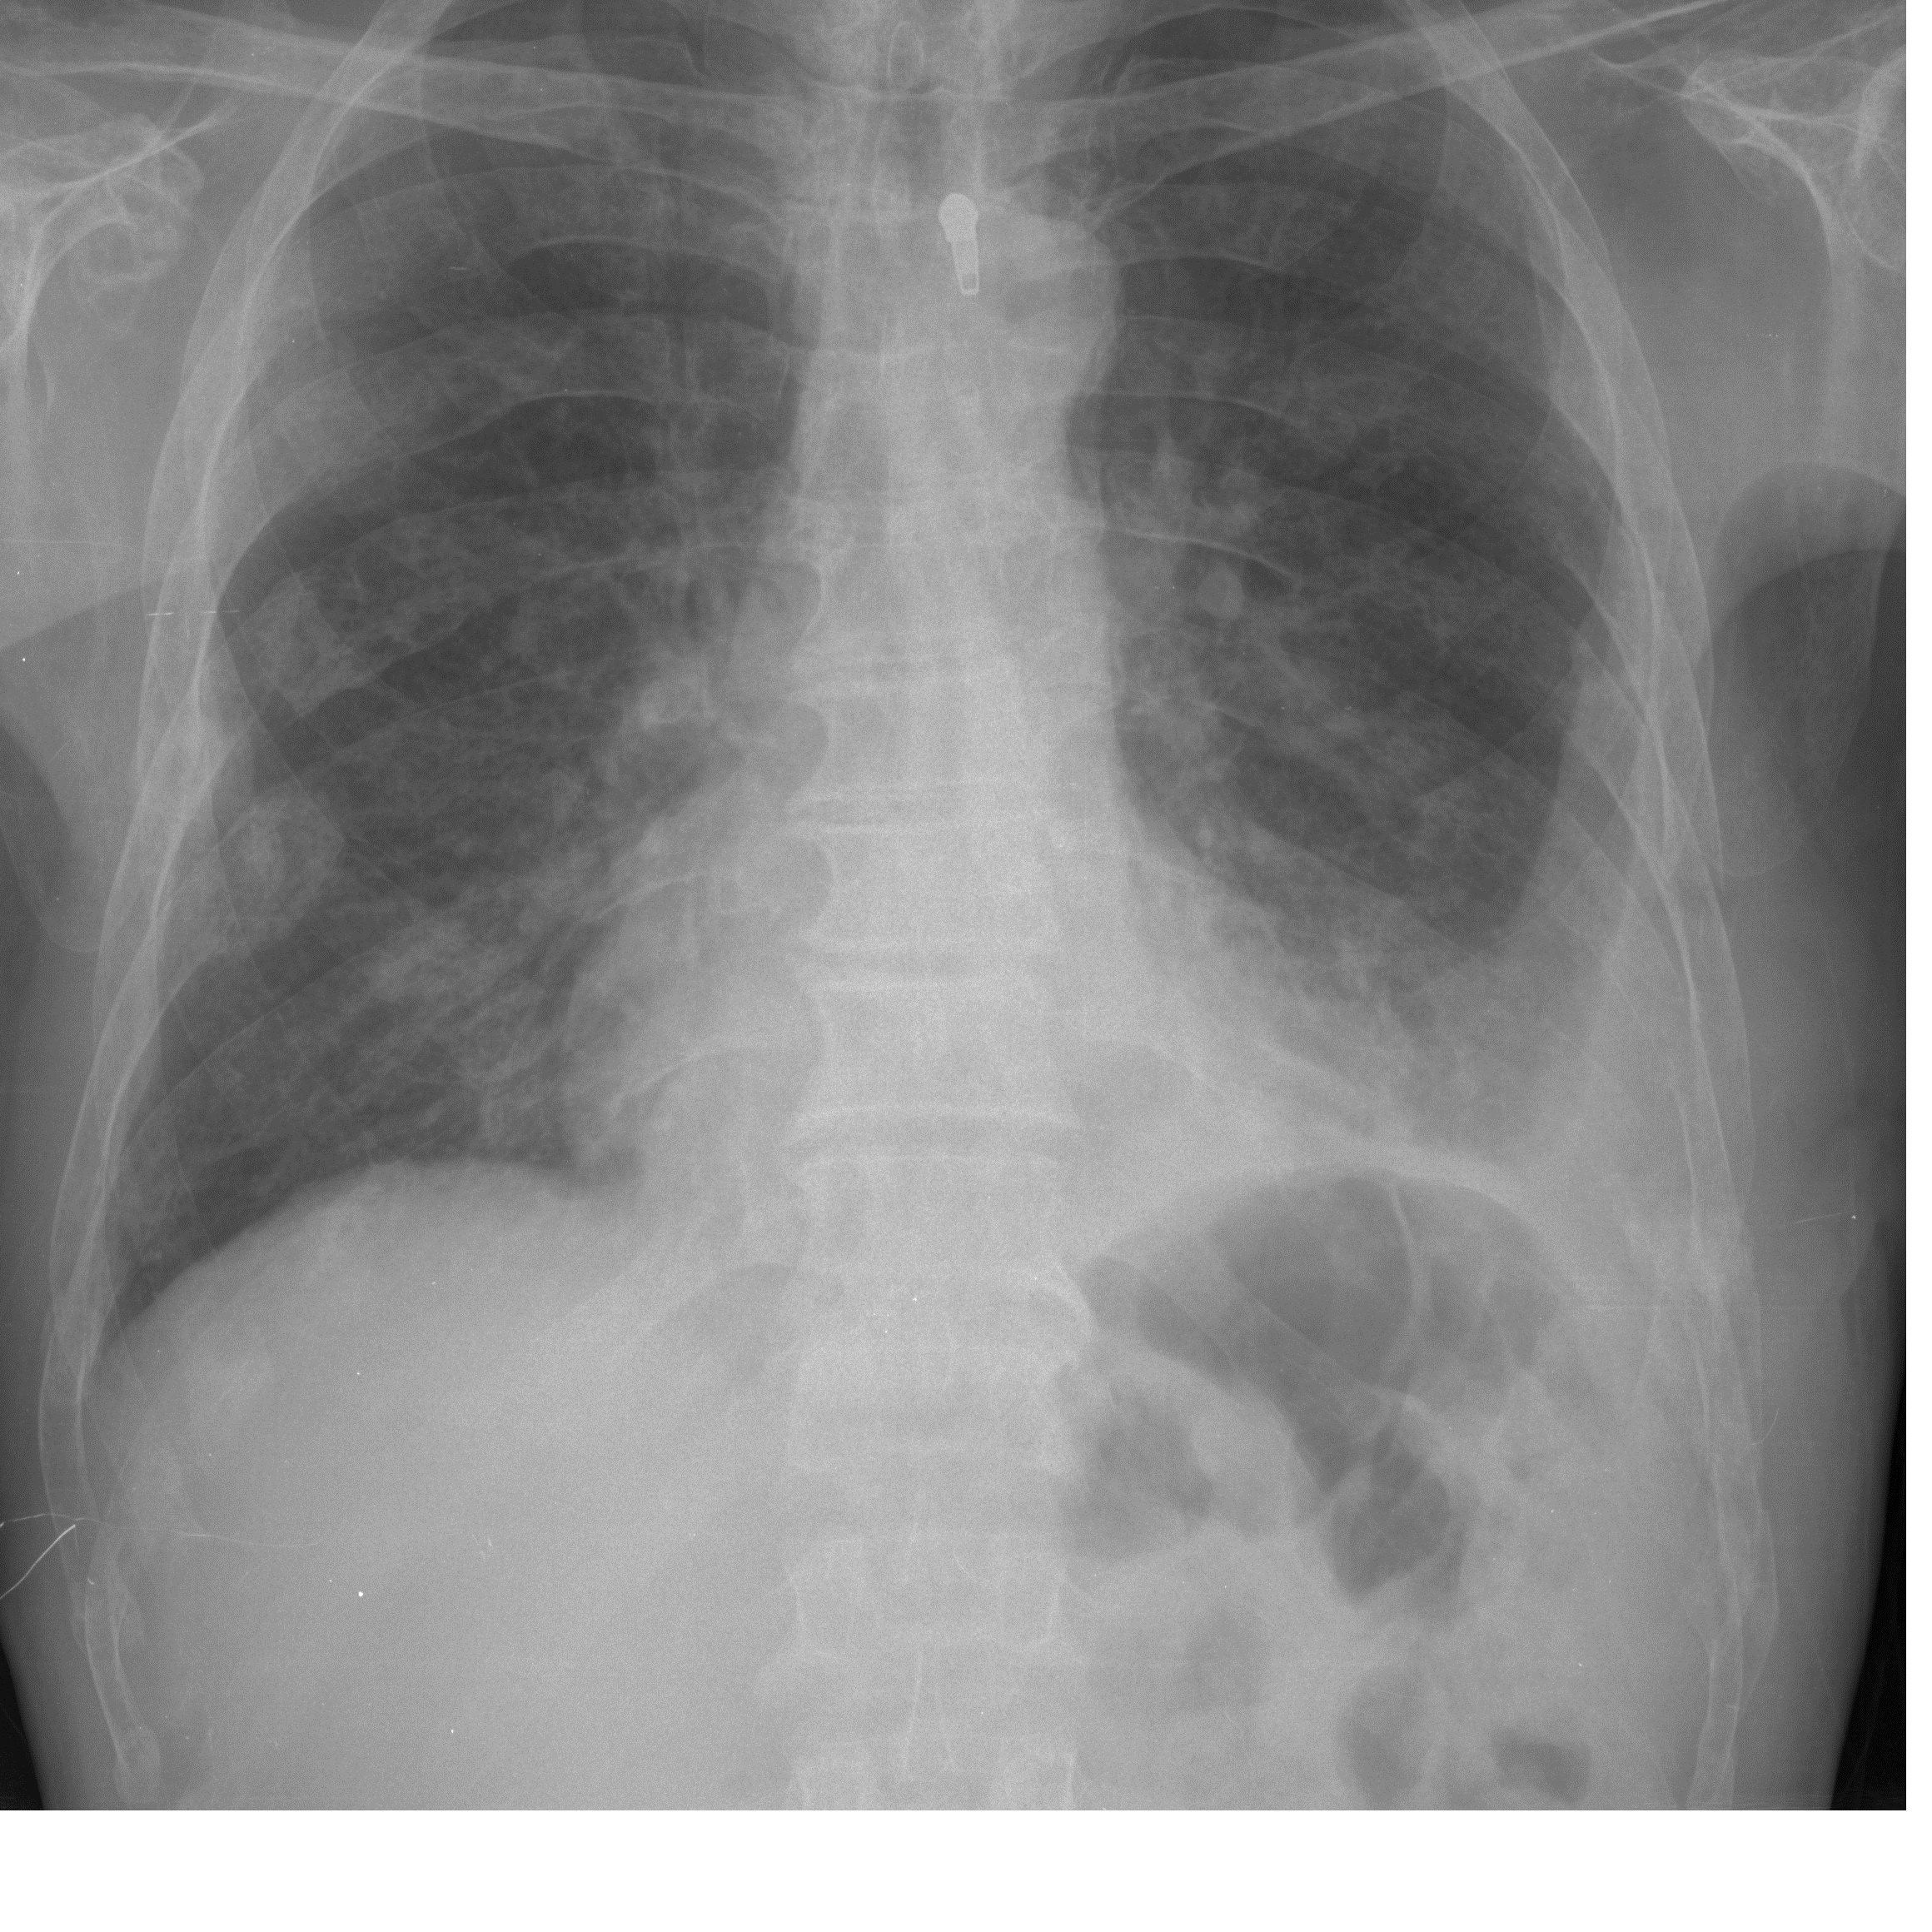

Flow Cytometry Method as a Diagnostic Tool for Pleural Fluid Involvement in a Patient with Multiple Myeloma